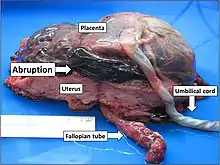

In the vast majority of cases, placental abruption is caused by the maternal vessels tearing away from the decidua basalis, not the fetal vessels. The underlying cause is often unknown. A small number of abruptions are caused by trauma that stretches the uterus. Because the placenta is less elastic than the uterus, it tears away when the uterine tissue stretches suddenly. When anatomical risk factors are present, the placenta does not attach in a place that provides adequate support, and it may not develop appropriately or be separated as it grows. Cocaine use during the third trimester has a 10% chance of causing abruption. Though the exact mechanism is not known, cocaine and tobacco cause systemic vasoconstriction, which can severely restrict the placental blood supply (hypoperfusion and ischemia), or otherwise disrupt the vasculature of the placenta, causing tissue necrosis, bleeding, and therefore abruption.[9]

In most cases, placental disease and abnormalities of the spiral arteries develop throughout the pregnancy and lead to necrosis, inflammation, vascular problems, and ultimately, abruption. Because of this, most abruptions are caused by bleeding from the arterial supply, not the venous supply. Production of thrombin via massive bleeding causes the uterus to contract and leads to DIC.[9]

The accumulating blood pushes between the layers of the decidua, pushing the uterine wall and placenta apart. When the placenta is separated, it is unable to exchange waste, nutrients, and oxygen, a necessary function for the fetus's survival. The fetus dies when it no longer receives enough oxygen and nutrients to survive.[9]

Placental abruption is suspected when a pregnant mother has sudden localized abdominal pain with or without bleeding. The fundus may be monitored because a rising fundus can indicate bleeding. An ultrasound may be used to rule out placenta praevia but is not diagnostic for abruption.[8] The diagnosis is one of exclusion, meaning other possible sources of vaginal bleeding or abdominal pain have to be ruled out in order to diagnose placental abruption.[5] Of note, use of magnetic resonance imaging has been found to be highly sensitive in depicting placental abruption, and may be considered if no ultrasound evidence of placental abruption is present, especially if the diagnosis of placental abruption would change management.[16]

- Class 0: Asymptomatic. Diagnosis is made retrospectively by finding an organized blood clot or a depressed area on a delivered placenta.